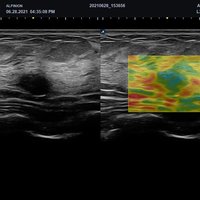

Das X-CUBE 70 bietet modernste Technologien für eine objektive und akkurate Diagnose. Intelligente klinische Module heben das System auf ein neues diagnostisches Niveau. Es erweitert Ihre Fähigkeiten und die Bandbreite Ihrer Möglichkeiten. Dazu gehören Module wie MicroView, point Shear Wave Elastographie (pSWE), oder auch die Kontrastmittelsonographie.

• L3-12X (3-12 MHz) für Ultraschalluntersuchungen in Bereichen MSK, Vaskulär, Weichteile, Pädiatrie, EM

• L3-8H (3-8 MHz) für Ultraschalluntersuchungen in Bereichen Brust, EM, MSK, Vaskulär, Weichteile